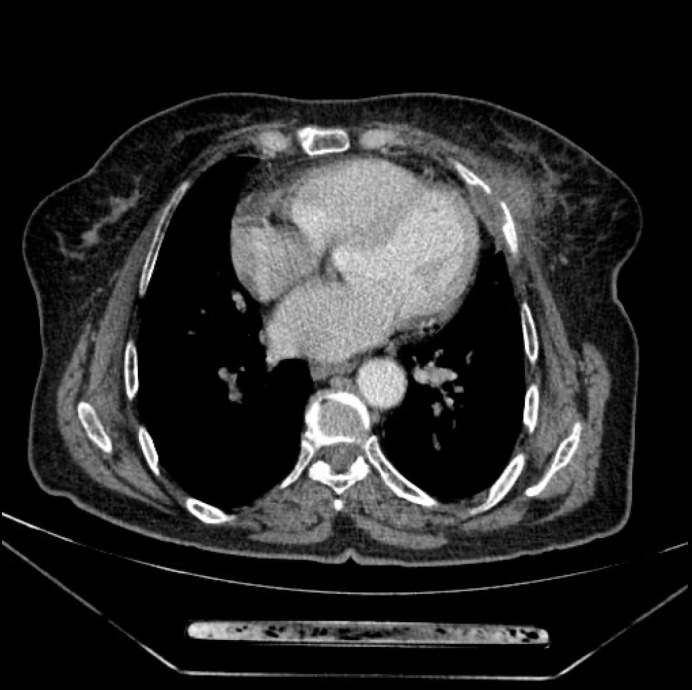

Tuberculosis (TB) of the rib is an uncommon manifestation of extrapulmonary TB that can pose significant diagnostic challenges, especially when presenting as a breast mass. We report the case of a 74-year-old woman who presented with a left breast lump, initially suspected to be a plasmacytoma due to its imaging characteristics and clinical history. The mass was surgically excised, and histopathological analysis revealed granulomatous inflammation with caseous necrosis, suggesting TB. TB-polymerase chain reaction confirmed the diagnosis, despite negative Ziehl-Neelsen staining. The patient was treated with anti-tubercular therapy for twelve months, resulting in a favorable clinical outcome. This case highlights the importance of considering rib TB in the differential diagnosis of breast masses, particularly in endemic areas, and underscores the role of comprehensive diagnostic evaluations for timely and effective treatment.